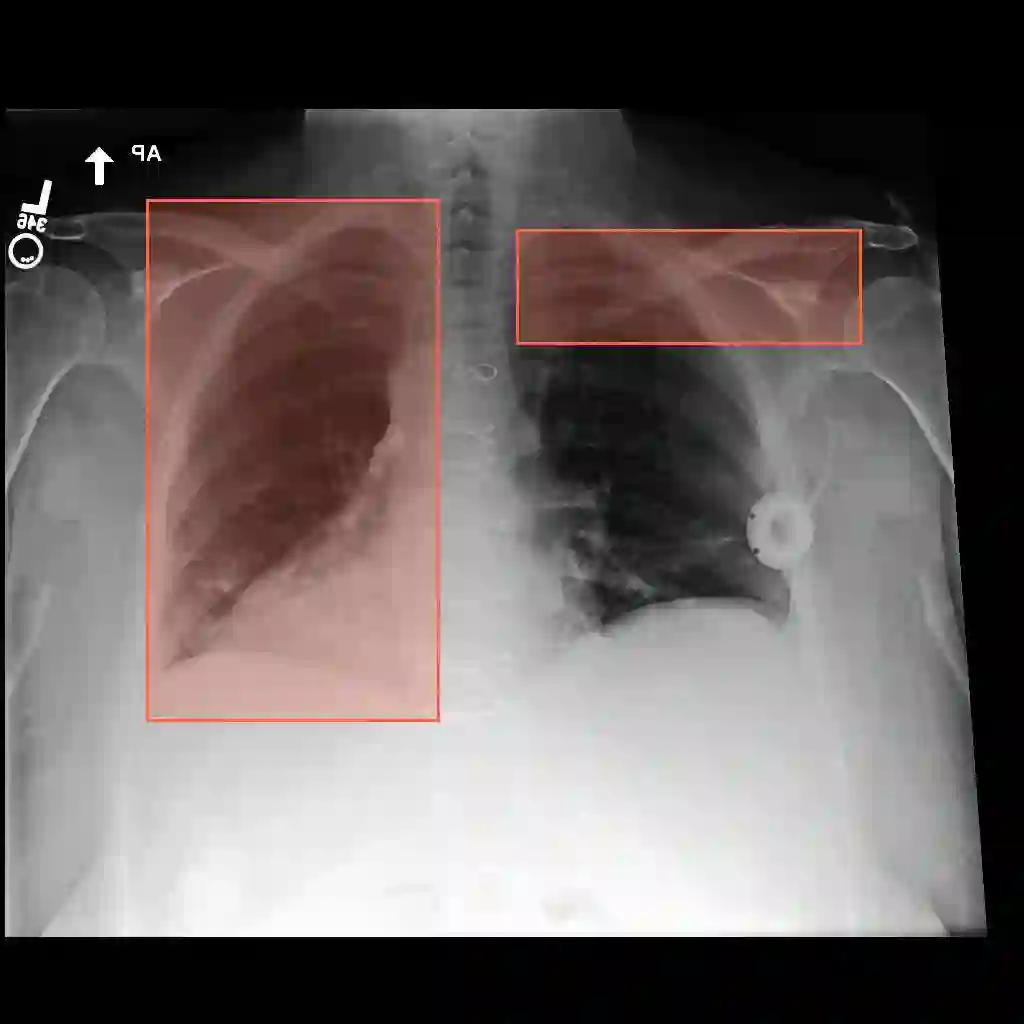

Multimodal medical large language models have shown impressive progress in chest X-ray interpretation but continue to face challenges in spatial reasoning and anatomical understanding. Although existing grounding techniques improve overall performance, they often fail to establish a true anatomical correspondence, resulting in incorrect anatomical understanding in the medical domain. To address this gap, we introduce AnatomiX, a multitask multimodal large language model explicitly designed for anatomically grounded chest X-ray interpretation. Inspired by the radiological workflow, AnatomiX adopts a two stage approach: first, it identifies anatomical structures and extracts their features, and then leverages a large language model to perform diverse downstream tasks such as phrase grounding, report generation, visual question answering, and image understanding. Extensive experiments across multiple benchmarks demonstrate that AnatomiX achieves superior anatomical reasoning and delivers over 25% improvement in performance on anatomy grounding, phrase grounding, grounded diagnosis and grounded captioning tasks compared to existing approaches. Code and pretrained model are available at https://github.com/aneesurhashmi/anatomix